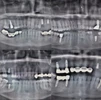

Implant tedavisi

Periimplantitis

Peri-İmplant Mukozitis